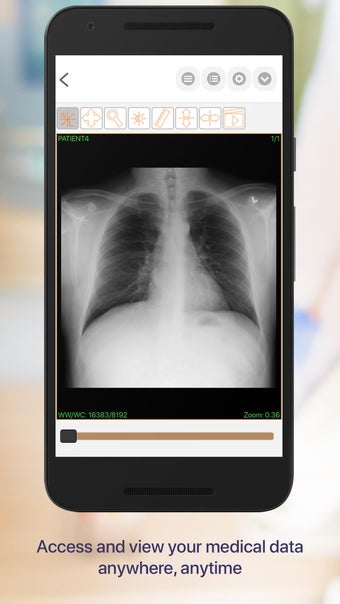

Carepassport là một ứng dụng Android cung cấp cho bệnh nhân một giải pháp toàn diện để quản lý dữ liệu y tế của họ. Ứng dụng cho phép bệnh nhân truy cập và lưu trữ an toàn dữ liệu y tế của mình, lên lịch hẹn, xem hình ảnh y tế, báo cáo xét nghiệm và lâm sàng từ các nhà cung cấp khác nhau, và chia sẻ chúng bằng công nghệ tính toán di động tiên tiến. Với Carepassport, bệnh nhân có thể dễ dàng quản lý nhu cầu chăm sóc sức khỏe của mình chỉ với vài lần chạm trên thiết bị di động của họ.

Một trong những tính năng quan trọng nhất của ứng dụng là việc truy cập dữ liệu y tế một chạm dễ dàng. Bệnh nhân có thể truy cập dữ liệu y tế của mình hoặc dữ liệu đại diện gia đình một cách an toàn và nhanh chóng, làm cho nó trở thành một công cụ tuyệt vời để quản lý lịch sử bệnh án của họ. Ứng dụng cũng cho phép người dùng tìm kiếm các phòng khám và bệnh viện gần đó, lên lịch hẹn, và thậm chí nhận chỉ đường đến cuộc hẹn của họ qua Uber. Ngoài ra, bệnh nhân có thể giao tiếp với nhà cung cấp chăm sóc của họ qua tin nhắn an toàn, chia sẻ hình ảnh y tế và cho phép thành viên gia đình truy cập dữ liệu y tế của họ thông qua cài đặt proxy an toàn. Cuối cùng, ứng dụng cung cấp tài liệu giáo dục liên quan đến chăm sóc sức khỏe và có thể kết nối với các thiết bị đeo được hoặc nhập dữ liệu y tế thủ công.